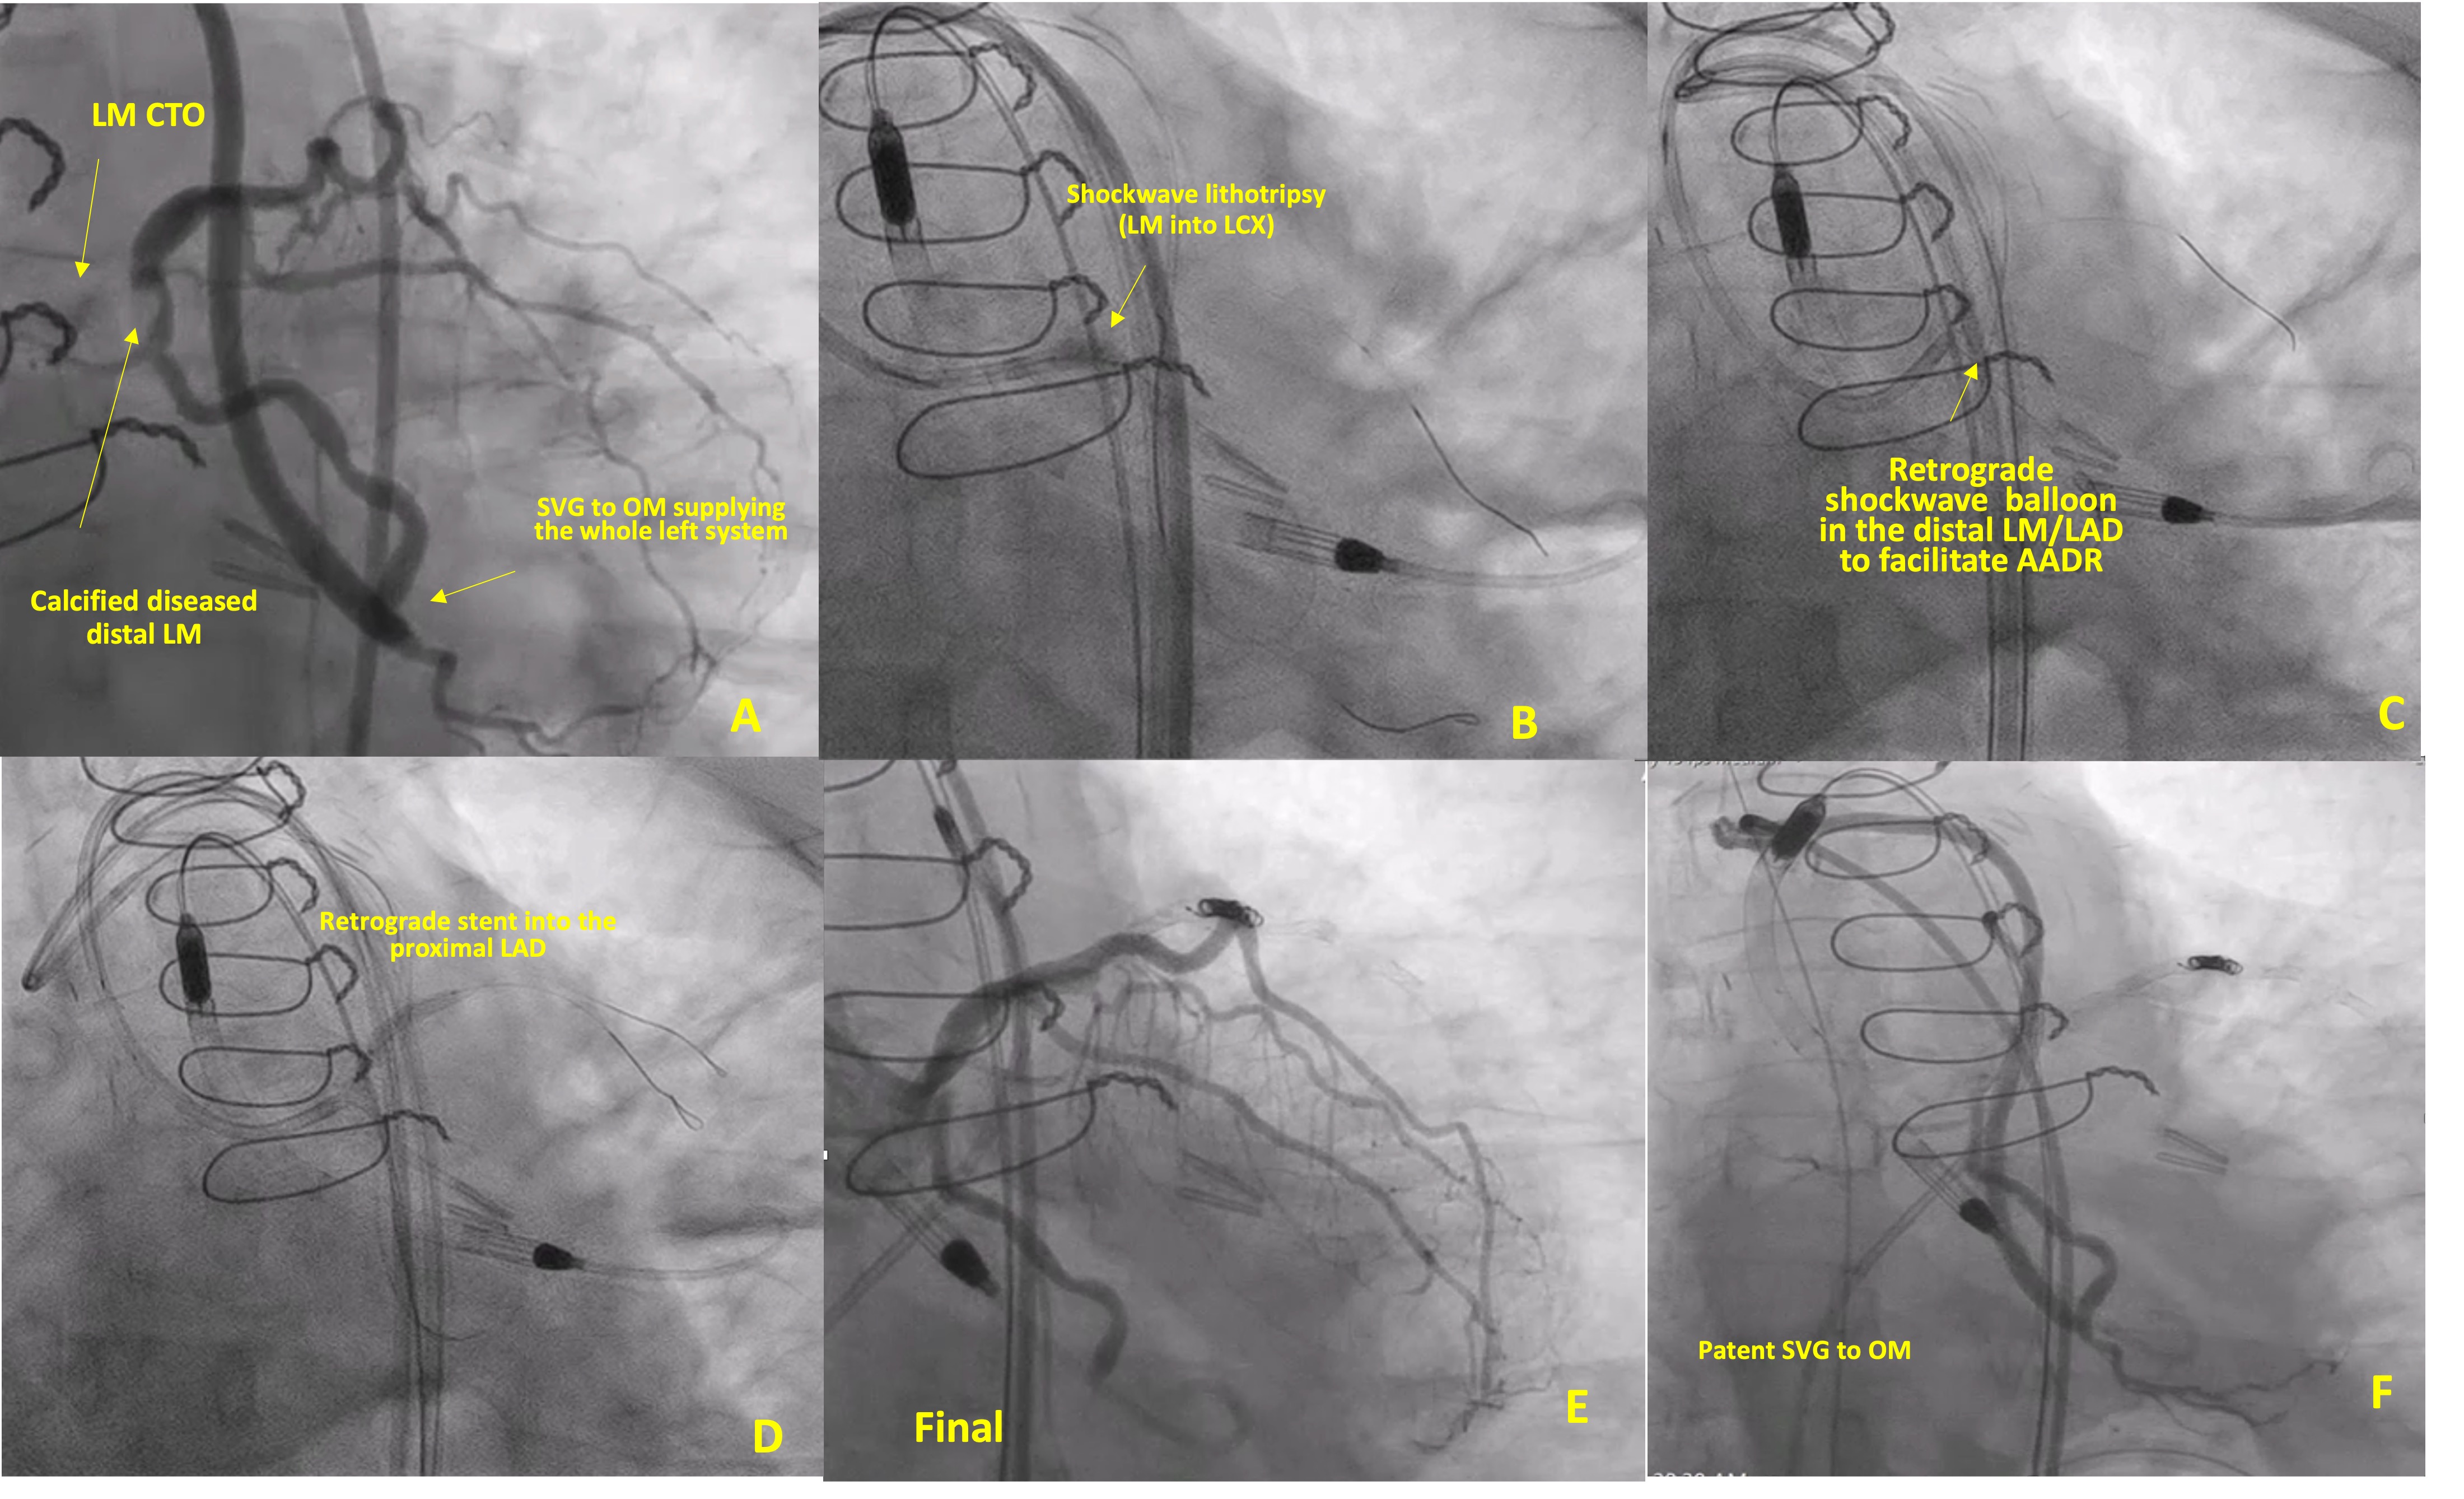

Right heart catheterization showed normal hemodynamics. We inserted an Impella CP (Abiomed) through the left femoral artery due to the risk of hemodynamic compromise with the retrograde approach through the only graft supplying the left system. We placed two 8 French 45-cm long sheaths through the right femoral artery. Multiple antegrade attempts failed. Multiple retrograde attempts failed due to the blunt distal cap and the difficult angle of penetration. Eventually, an Astato 20 (Asahi Intecc) wire crossed into the left circumflex artery (LCX). We used Shockwave lithotripsy balloon angioplasty from the LM into the LCX in an attempt to fracture the calcium at the distal LM to facilitate reentry into the LAD, but this also failed (Figure 1B, Video 3). We attempted the antegrade antegrade dissection re-entry technique (AADR)2 by inflating regular and cutting balloons placed retrogradely into the LAD and attempting to puncture towards it, but this also failed. Lithotripsy performed retrogradely over a Grand Slam wire (Asahi Intecc) also failed to facilitate AADR (Figure 1C, Figure 2A).

We delivered a stent retrogradely to the LAD delivered as a target for the antegrade wire (stent target technique) (Figure 2B). We deployed a 3-mm stent into the proximal LAD over the retrograde wire (Figure 1D, Video 4). We then crossed from the LM into the LAD stent and performed intravascular ultrasound (IVUS)-guided PCI of the LM to the LAD (Figure 1E). We detected a perforation of a small diagonal branch coiled with multiple Interlock coils (Boston Scientific). Final images showed excellent Thrombolysis in Myocardial Infarction (TIMI) 3 flow from LM into the LAD (Figure 1F, Video 5) and patent saphenous vein grafts (SVG) to the OM (Video 6). We removed the Impella CP device after 36 hours and closed the site with the MANTA device (Teleflex). The patient was doing well at the 6-month follow-up.

Retrograde lithotripsy (Figure 2A) can be helpful in calcified LM CTOs supplied by a large collateral (typically an SVG) that allows delivery of the balloon to the distal cap, which can facilitate AADR through microfractures of the calcified CTO body. The stent target technique (Figure 2B) we describe can be useful in LM CTOs supplied by a large SVG through which a stent can be delivered distally to the distal cap to provide a target for the antegrade wire after the failure of other techniques. It is similar to the stent-controlled antegrade and retrograde subintimal tracking (CART) technique that was abandoned due to difficulties when re-entering into the stent, sometimes leading to crossing through the side of the stent struts. However, the stent target technique does not involve stenting the extraplaque space; instead, the stent is implanted into the true lumen distal to the distal cap to provide a target for antegrade wiring. Performing the “stent target” technique requires strong support to facilitate retrograde equipment delivery.